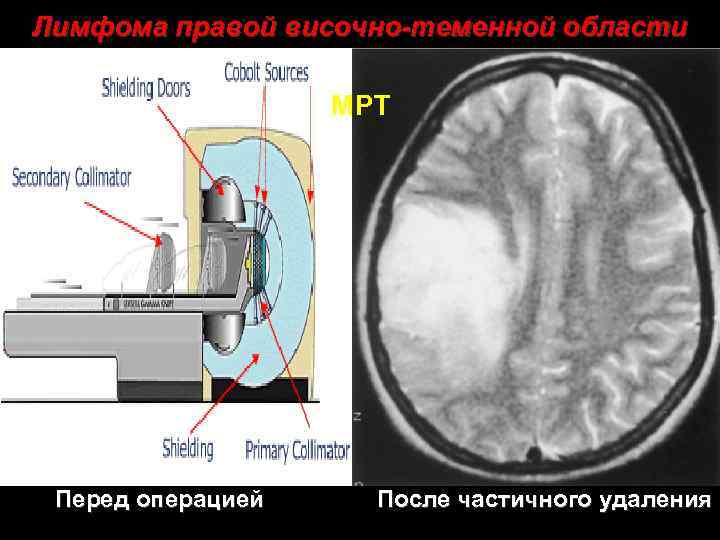

Лимфома правой височно-теменной области МРТ Перед операцией После частичного удаления 31